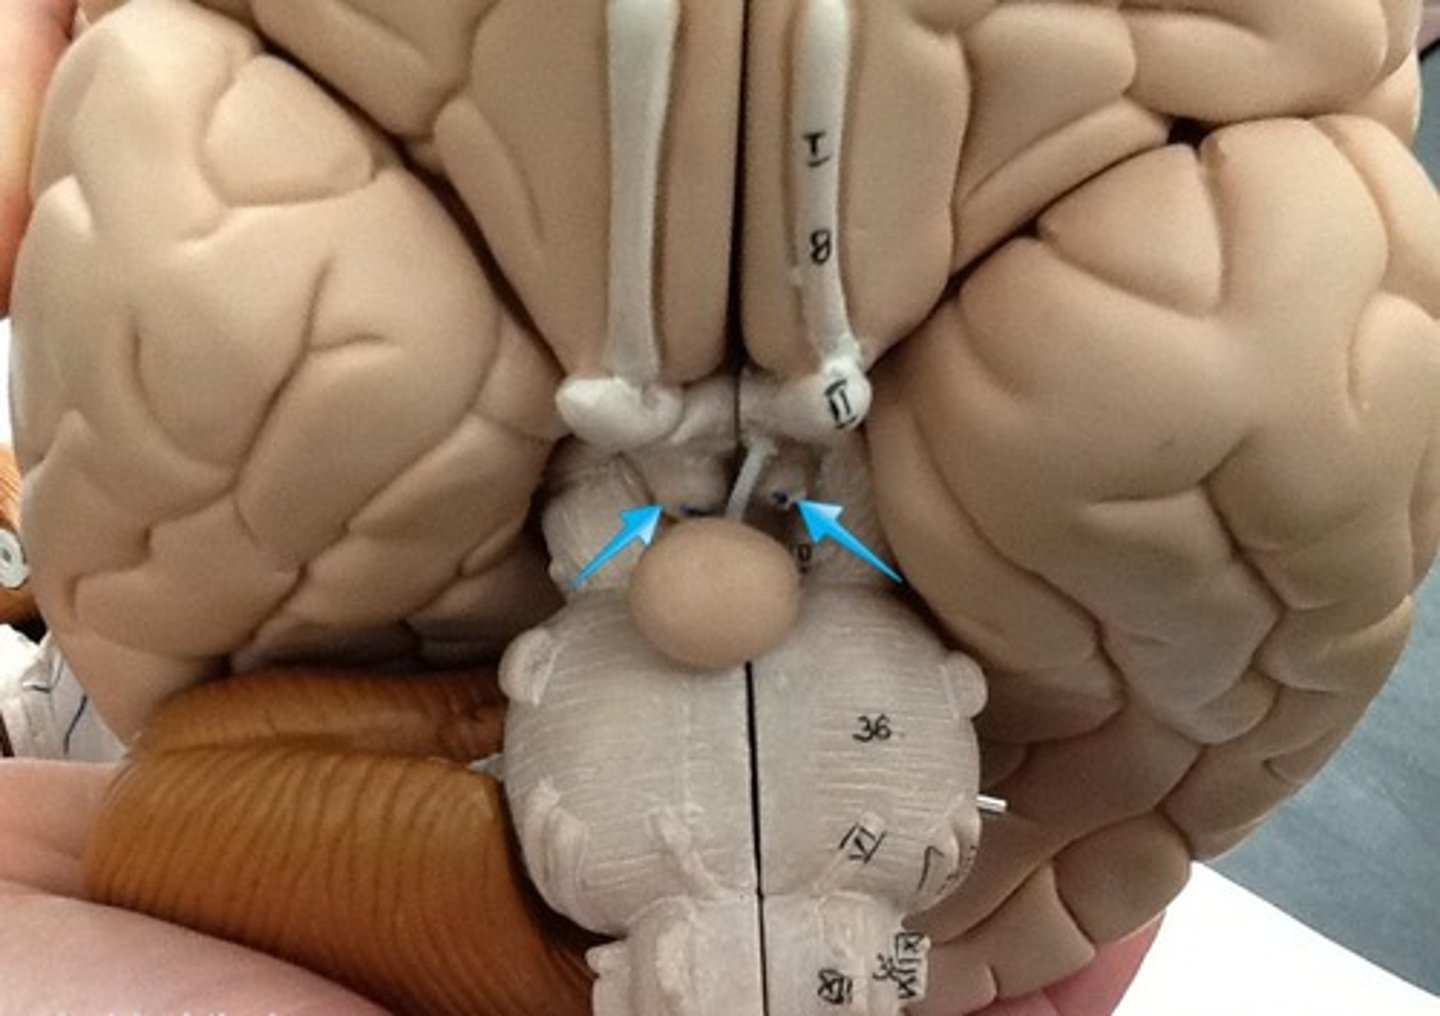

optic chiasm

Mammillary body

olfactory nerve

optic nerve

oculomotor nerve

trochlear nerve

trigeminal nerve

abducens nerve

facial nerve

vestibulocochlear nerve

glossopharyngeal nerve

vagus nerve

accessory nerve

hypoglossal nerve

optic tract